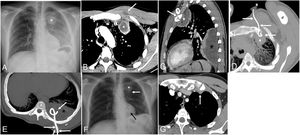

A 29-year-old patient presented to our hospital with fever and left upper chest swelling. A chest radiograph showed a left pleural effusion and an ill-defined focal lesion in the left superior hemithorax (Fig. 1A). A thoracic CT showed an extrapleural fluid collection extending from the left sternochondral joint of the first rib towards the left upper lobe as well as small fluid rim-enhancing collections involving the left pectoralis muscles, consistent with soft-tissue abscesses (Fig. 1B). There was also a loculated posterior ipsilateral pleural effusion (Fig. 1C). The diagnosis of a septic sternochondral arthritis of the first rib complicated with an ipsilateral pleural empyema was made. It was decided to insert pigtail catheters both into the extrapleural fluid collection and into the left pleural space under CT guidance in a single procedure (Fig. 1D and E). The procedure was uneventful and demonstrated Staphylococcus aureus, both in the extrapleural fluid collection and in the left pleural effusion. The patient responded well to antibiotic therapy, and surgical debridement was not deemed necessary (Fig. 1F and G).

(A) Chest radiograph (posteroanterior view) shows an ill-defined lesion projected over the sternochondral joint of the first left rib (asterisk). Note the increased density of the left hemithorax due to an ipsilateral pleural effusion. (B) Axial thoracic CT image (mediastinal window) shows an extrapleural fluid collection (asterisk) and demonstrates a small low-attenuation lesion in the left pectoralis major muscle (arrow). (C) Sagittal thoracic CT image (mediastinal window) better shows the extrapleural fluid collection (white asterisk) originating in the first sternochondral joint (arrow) and a large loculated pleural effusion (black asterisk). (D) Axial thoracic maximum intensity projection (MIP) CT image shows a pigtail catheter (arrows) within the extrapleural fluid collection (asterisk). (E) Axial thoracic MIP image shows another pigtail catheter (arrows) within the left pleural effusion. (F) Chest radiograph (posteroanterior view) obtained 1 week after the insertion of the pigtail catheters (arrows) shows marked improvement. Note the reduction in size of the extrapleural lesion in the left upper hemithorax (asterisk). (G) Axial thoracic CT image (mediastinal window) performed 8 weeks after the insertion of the pigtail catheter shows complete resolution of the extrapleural collection and minimal residual thickening of the soft tissues surrounding the first sternochondral joint (arrow).